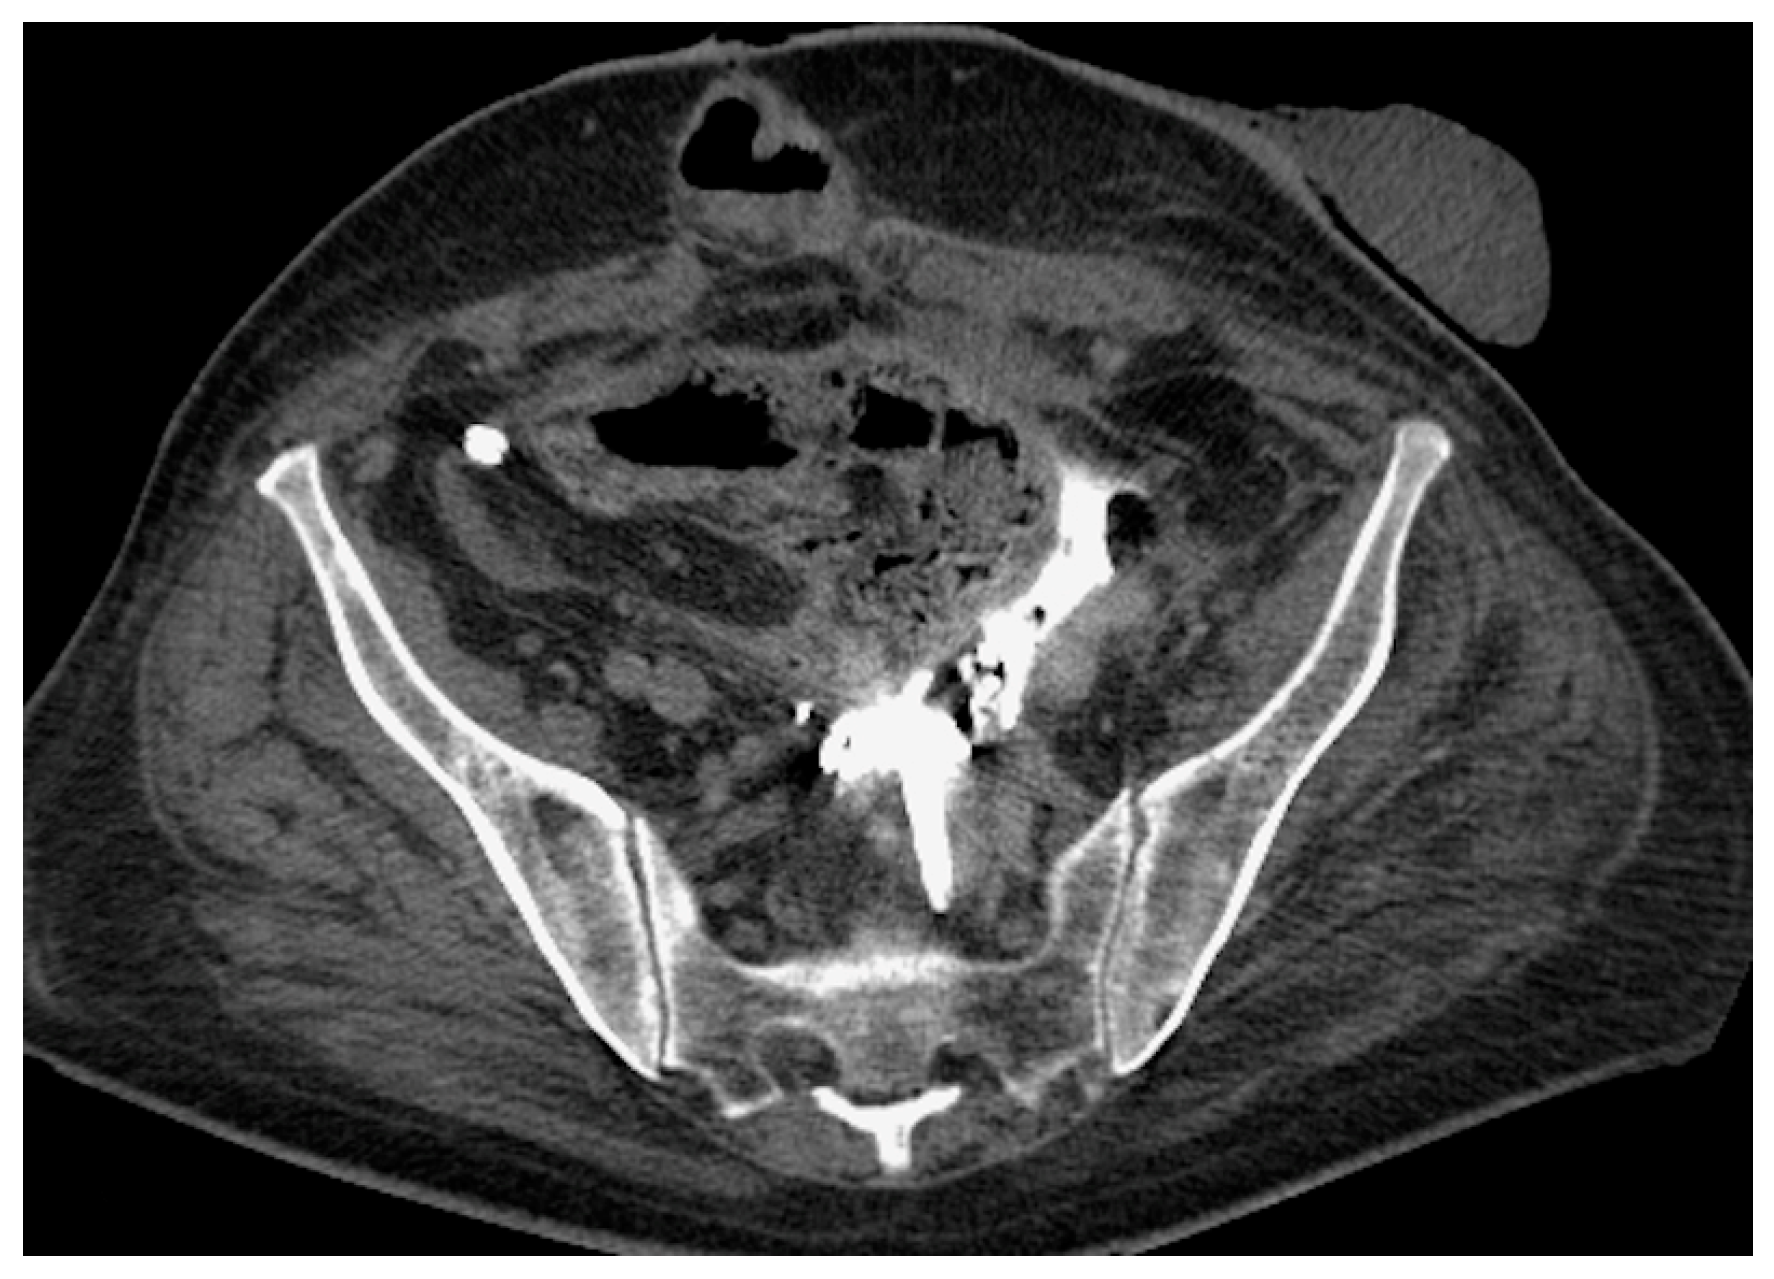

- Malposition: The malposition of a stent is defined as an incorrect position relative to initial placement, while displacement presents a subsequent occurrence in a device that was previously located in the correct position. A stent improperly positioned might assume a sub-pyelic position when the proximal end fails to reach the renal pelvis and a supravesical position when the distal end is detected within the ureter. The origins of this complication predominantly stem from the placement technique, whether it be endoscopy- or fluoroscopy-guided insertion. This underscores the need to verify the accurate positioning of the stent post-placement. Ensuring an adequate length is essential to reduce the occurrence of this complication (Figure 2, Figure 3, Figure 4, Figure 5 and Figure 6) [21,22].